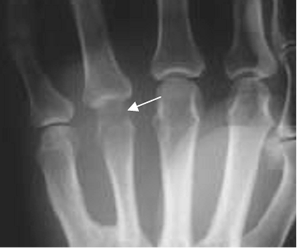

En las etapas subaguda y crónica, se produce erosión y destrucción ósea. Puede encontrarse también reacción perióstica en láminas. (16). (Fig 64 A, 64 B, 64 C y 64 D).

Fig 64 A. Artritis séptica.

Fig 64 B . Artritis séptica.

Rx AP. Artritis infecciosa del pulgar, con zonas de osteolisis en la base de la falange y la cabeza del metatarsiano. (Flechas). Hay edema asociado de los tejidos blandos.